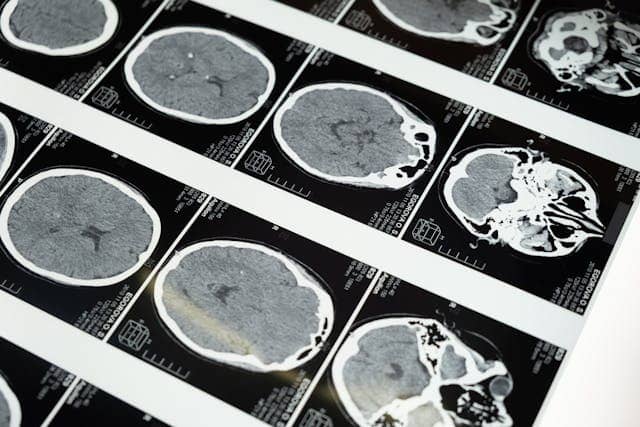

2. 뇌실내 출혈 (IVH, intraventricular hemorrhage)

34주 미만 조산아에서 주로 발생.

아기의 뇌 안에는 ‘뇌실’이라는 공간이 있습니다. 이 뇌실 아래쪽에는 ‘배아기질(Germinal Matrix)’이라는 아주 작고 섬세한 혈관들이 모여 있는 부위가 있습니다.

이 부위는 임신 32~34주 정도가 되면 자연스럽게 사라지지만, 그보다 이른 시기에 태어난 아기들은 이 부분이 아직 남아 있어서, 작은 충격이나 스트레스만으로도 출혈이 생기기 쉬운 상태인 겁니다.

이런 뇌실 내 출혈(IVH)은 대부분은 자연스럽게 회복되지만, 가끔 출혈이 많아져 뇌 안의 압력이 올라가거나,

혈액이 뇌 조직까지 스며들게 되면 조금 더 신경 써야 할 상황이 될 수 있습니다.

특히 1.5kg 이하의 미숙아 중 약 20~30%에서 출혈이 발생하고, 그 중 5% 정도는 중증 출혈로 이어질 가능성이 있습니다.

이 경우에는 시각, 청각, 몸의 움직임 조절 능력에도 영향을 줄 수 있기 때문에, 조기 발견과 꾸준한 관찰이 정말 중요합니다.

출혈이 심해서 뇌 바깥쪽까지 퍼질 경우, 주로 다리와 몸통의 움직임을 조절하는 부위가 영향을 받아 다리의 긴장도나 움직임에 어려움이 생길 수 있습니다. 이럴 땐 물리치료를 통해 도움을 받을 수 있습니다.

출혈이 3~4단계로 심화되면 운동 기능, 시각, 청각 손상 가능성이 높아집니다.

단계 설명

1단계 뇌막 밑 또는 배아기질에 국한된 출혈

2단계 뇌실 내 출혈 (50% 미만)

3단계 뇌실 확장 동반

4단계 출혈이 뇌실질까지 확장됨

3. 뇌실 주위 백질연화증 (PVL)

이건 조금 어려운 말일 수 있지만, 쉽게 말해 뇌의 중심부 근처에 있는 '백질'이라는 부위가 약해져서 손상되는 것입니다.

아직 혈관이 덜 자란 32주 미만의 아기는 뇌 안에 혈류가 닿지 않는 작은 구역들이 남아 있습니다.

이 부위는 산소가 부족하거나, 패혈증처럼 몸이 아픈 일이 생기면 뇌세포가 상처를 입고, 시간이 지나면서 그 부분에 "작은 낭포(물혹처럼 보이는 공간)"가 생기기도 합니다.

특히 이 백질 부위에는 "다리의 움직임을 조절하는 신경 통로(겉질척수로)"가 지나가는데, 이 부분이 손상되면 팔보다 다리 쪽 움직임에 더 큰 영향을 줄 수 있습니다.

특히 미숙아에서 저산소증 + 혈류 불안정으로 인해 발생. 주로 다리와 몸통을 지배하는 신경 섬유가 손상되어 양하지 마비로 이어질 수 있습니다.